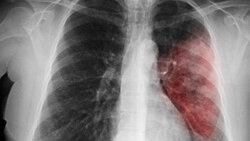

Как долго нужно пить антибиотики при пневмонии?

Раньше воспаление легких лечили 21 день. И это в том случае, если заболевание протекало без осложнений. Антибиотики при пневмонии обязательно вводили внутривенно или внутримышечно, а лечение проходило в больнице. Принципы современной терапии Сегодня подходы терапии существенно изменились. Воспаление легких в легкой и среднетяжелой форме лечат амбулаторно. Госпитализация в стационар требуется определенным больным: Длительность лечения В настоящее время пневмонию лечат преимущественно таблетками. Исключение...